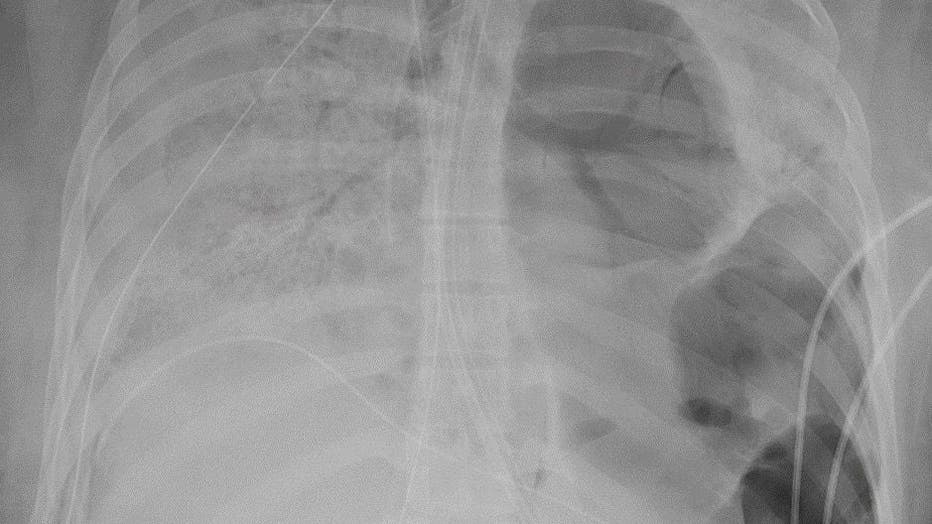

lung xray

Doctors said the COVID-19 patient, identified as a woman in her 20s, was otherwise pretty healthy. An X-ray of her lungs are pictured in a provided image. (Photo credit: Northwestern Memorial Hospital)